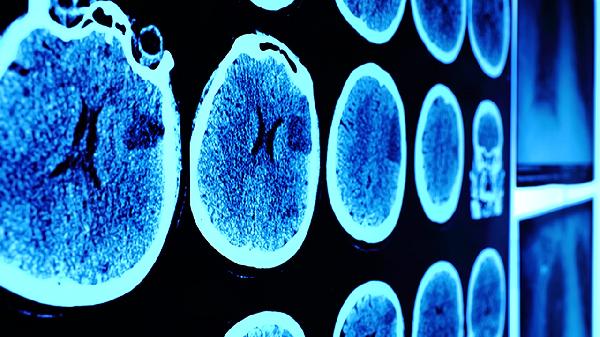

大脑失去记忆可通过认知训练、药物治疗、心理干预、生活方式调整、康复治疗等方式改善。记忆丧失可能由脑外伤、阿尔茨海默病、脑血管疾病、精神心理因素、营养缺乏等原因引起。